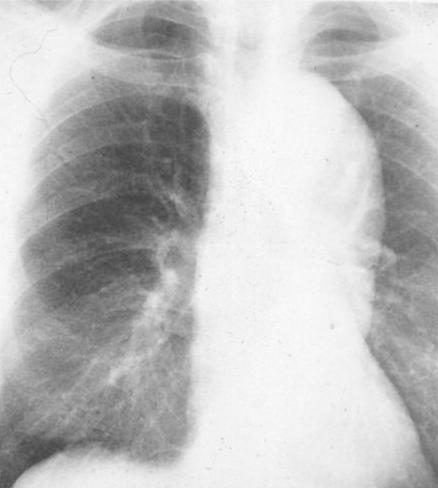

Radiologic Diagnosis of Thoracic Aortic Aneurysms

Radiologic Diagnosis of Thoracic Aortic Aneurysms Patricia Tung, Harvard Medical School Year III. Gillian Lieberman, MD. 2. www.aic.cuhk.edu.hk/web8/thoracic_aortic_aneurysm.htm. 12 Patricia Tung HMS III Gillian Lieberman, MD January 2005 CXR: Radiologic Findings ... Retrieve Doc

Aortic Aneurysm: A Rare Cause Of Ortner's Syndrome

Thoracic aortic aneurysms. Thus, this syndrome is also Chest X-ray showed a large opacity in the left upper zone. size of the thoracic aortic aneurysm is a key parameter for predicting the risks of complications like dissection, ... Fetch Document

Thoracic Pathology Aortic Dissection And Aneurysms

A thoracic aortic aneurysm may be clinically silent, but may also cause chest and back pain. The risk of aneurysm rupture is high once if the aneurysm reaches a certain size. Chest X-ray Computerized Tomography (CT) Scan Angiography. Treatment ... Retrieve Full Source

Aortic Aneurysm Guide - Cleveland Clinic

Aortic aneurysm. Thoracic aorta aneurysms occur in the portion of the aorta in the chest. A thoracic aortic aneurysm can develop in the aortic root, the ascending aorta, The aneurysm is usually discovered by X-ray during a routine health exam for some other, ... Return Document